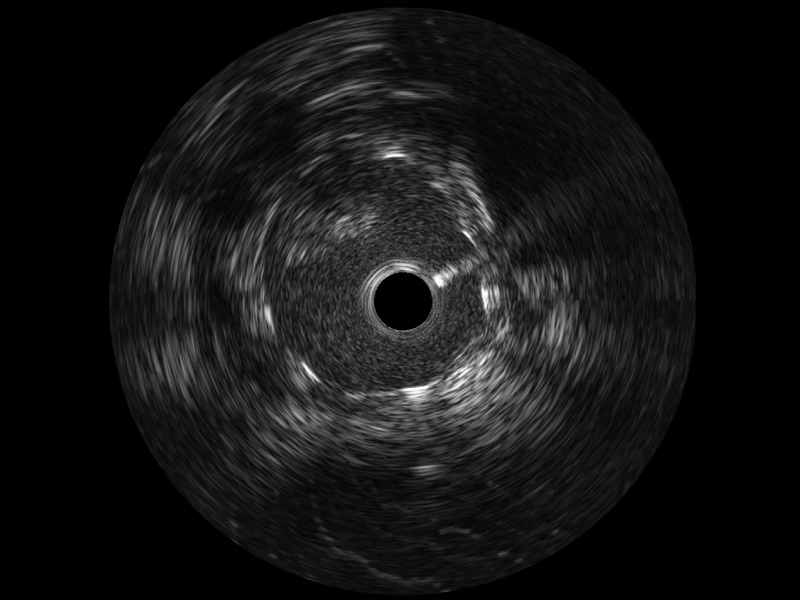

• 传统IVUS图像

对比传统IVUS导管成像,不朽情缘宽频IVUS图像的近场支架梁显影更细腻,远场中膜外血管仍清晰可辨,兼顾远中近,兼顾分辨力与穿透深度